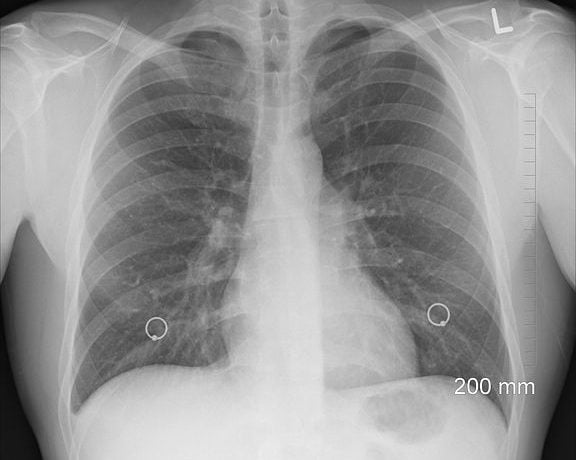

Pneumonia

Pneumonia este o infecție respiratorie acută a țesutului plămânilor (alveoli), determinând acumulare de lichid și puroi la acest nivel. Pentru că sacii alveolari afectați sunt responsabili de schimbul de oxygen, inflamarea acestora poate împiedica umplerea lor corespunzătoare cu oxygen, ceea ce poate conduce la oxigenare